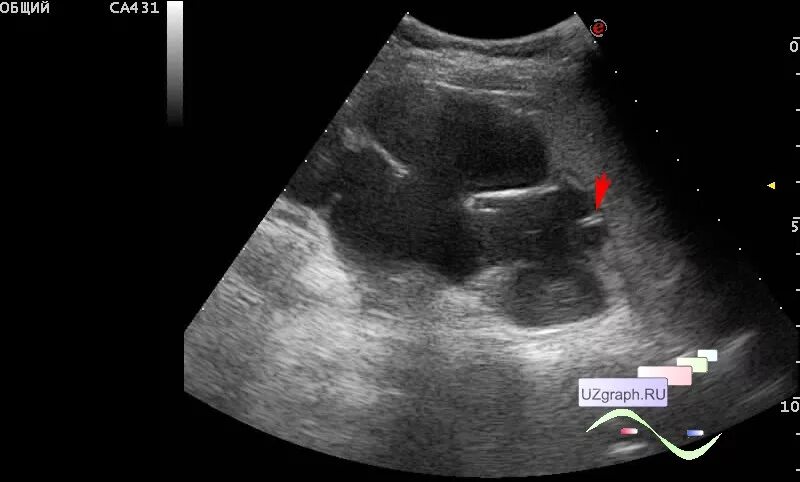

Нефростома в почке что это